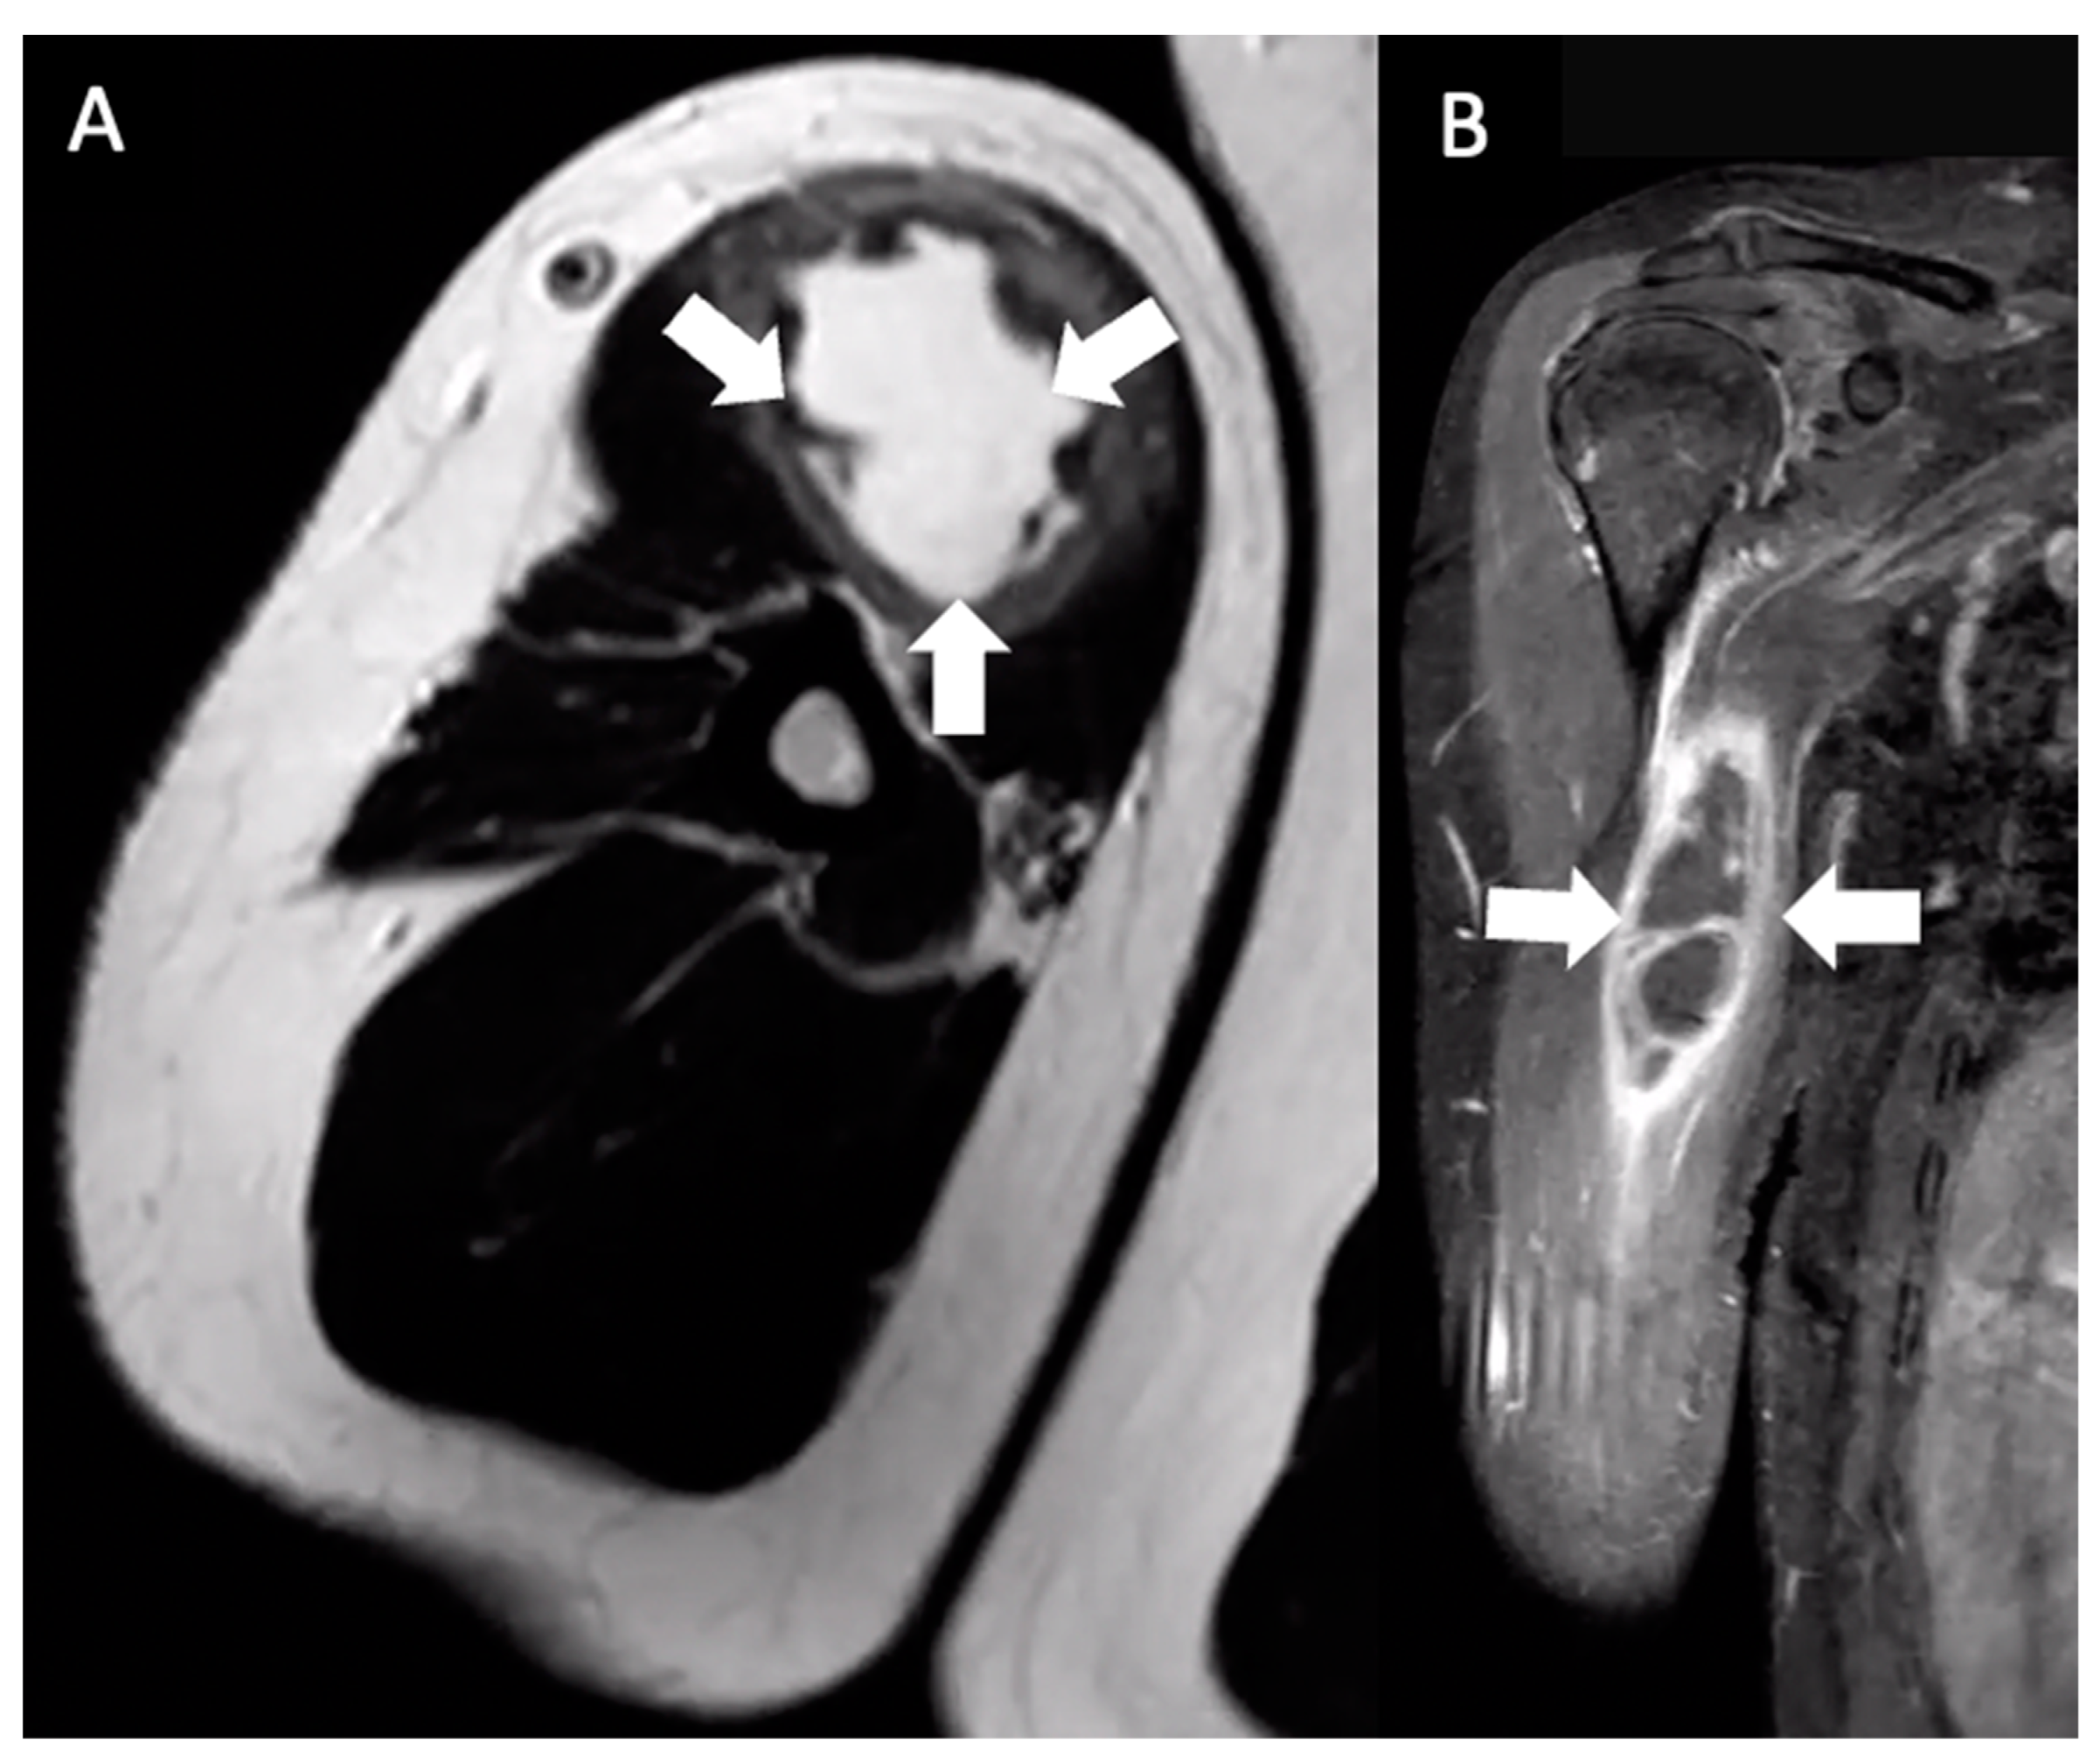

His primary care physician referred him to an orthopedic surgeon to evaluate his right upper arm. Physical examination at that time, two weeks later, was notable for a firm, clinically circumscribed, nontender mass in the right upper arm. Right shoulder active range of motion (ROM) was within the normal range, but passive range of motion was decreased. Given the MRI findings of an indeterminate mass, the orthopedic surgeon elected for a needle aspiration. An ultrasound-guided needle aspiration yielded 30 mL of turbid brown fluid, and a biopsy showed fibromuscular tissue with a chronic lymphoplasmacytic inflammatory infiltrate comprised of lymphocytes, plasma cells, and eosinophils. Immediately after the aspiration, there was a subjective improvement in the size of the swelling; as the patient stated, “the mass was not a golf-ball anymore”. However, a second MRI taken two weeks after the needle aspiration showed persistent 10 × 3.1 × 1.9 cm ill-defined fluid signals and peripheral enhancement in the proximal right biceps in the same location as on the first MRI (Figure 2). Given the persistent MRI findings and unclear diagnosis, a complete excision of the mass was accomplished in the following week. The pathology showed soft tissue and skeletal muscle with mild fibrosis and aggregates of inflammatory cells, consisting mostly of lymphocytes, plasma cells, and histiocytes. The cells showed no atypia or cytological features of malignancy (Figure 3).

As noted in the pathology reports, the lymphoplasmacytic cells and T-cell and B-cell populations found in the inflammatory infiltrate suggest a chronic state of inflammation with the formation of a granuloma [16]. Although the patient reported that the booster dose was injected into the right deltoid, he presented with a mass in the proximal-anteromedial right biceps. We hypothesize that the APCs containing fragments of foreign antigens traveled through lymphatic vessels of the upper limb and transmigrated into the surrounding tissue prior to draining into the adjacent lymph node, given the absence of lymph node involvement in Figure 3 [17]. It is this secondary edematous response that is hypothesized to have led to the palpable pseudo-tumors in these patients. The other possibility is that the injection missed its mark.

Figure 3. (A) Low-power view shows soft tissue and skeletal muscle with mild fibrosis and aggregates of inflammatory cells, consisting mostly of lymphocytes arranged in serpentine and nodular patterns and granulation tissue (blue arrows in the skeletal muscle; black arrows in the fibrous soft tissue). (B,C) High-power views show the inflammatory infiltrates consisting mostly of lymphocytes, plasma cells, and histiocytes. The cells show no atypia or cytological features of malignancy. Multiple special immunohistochemical studies were performed; Epstein–Barr virus in situ hybridization, Grocott methenamine silver, acid-fast bacillus, and human herpesvirus-8 were negative, ruling out viral and fungal-associated conditions. Lymphoid markers and CyclinD1 were performed and were negative, ruling out hematopoietic or histiocytic neoplasms. Histocytologic findings are most consistent with deep chronic inflammatory tumefaction or inflammatory pseudo-tumor.